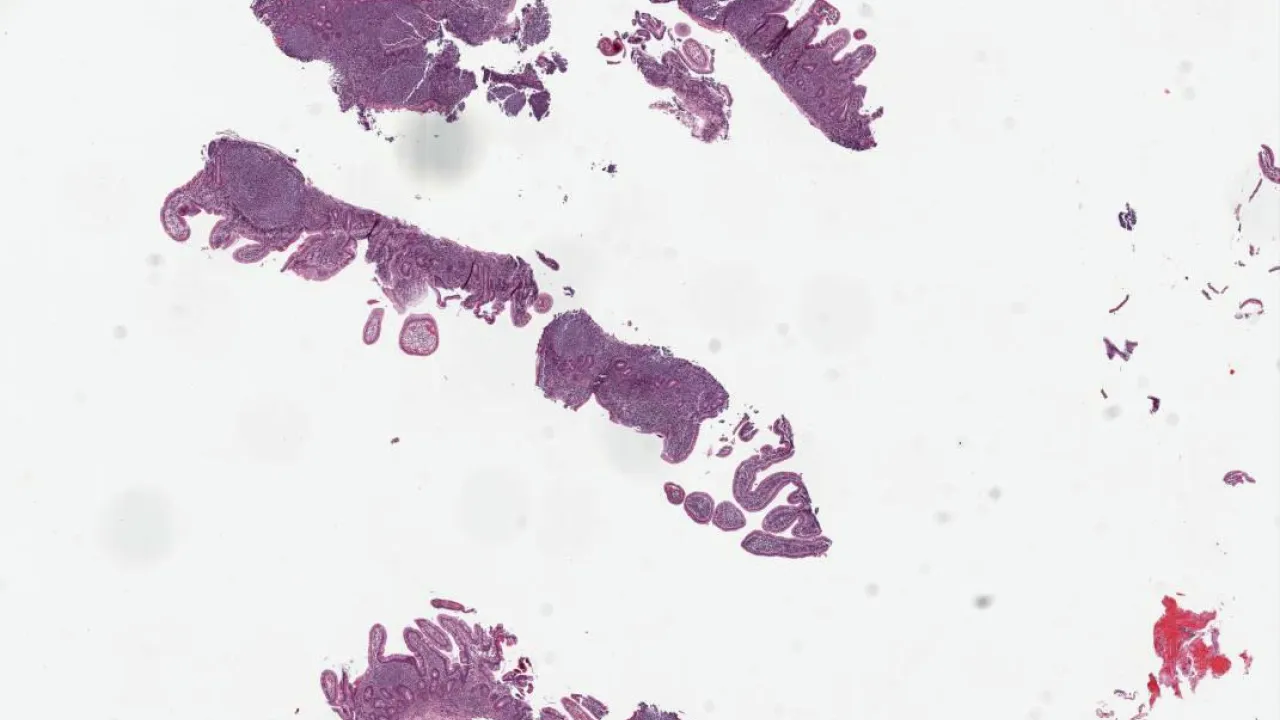

Lymph Node, Nodular lymphocyte predominant Hodgkin lymphoma, H&E stain